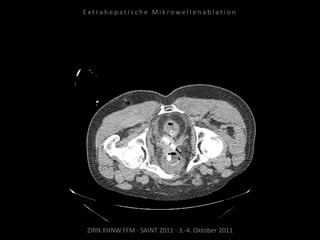

Kontrollbildgebung:

CT 18.08.2010

MRT 08.09.2010

Restvitalität von 2 Metastasen.

Nadelposition unzureichend?